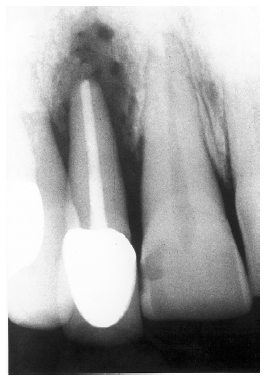

Residual Root Fragments

If the tooth is not completely removed, e.g., because of a root fracture or residual deciduous tooth root, a residual tooth fragment may persist. These fragments can be distinguished from socket sclerosis by the presence of a root canal and an intact periodontal ligament space. Figure 20 illustrates the appearance of a residual root and intact ligament space following the extraction of a mandibular first molar.

Figure 20 - Residual Tooth Fragment

Figure 20